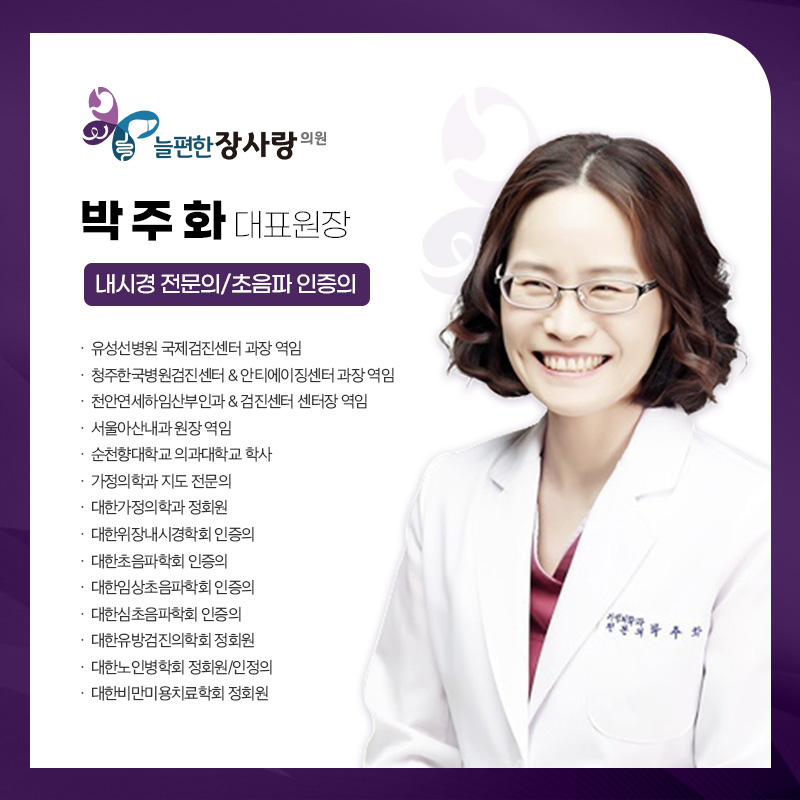

늘편한장사랑의원의

대장내시경 검사

늘편한장사랑의원에서는 풍부한 임상 경험을 바탕으로

여의사가 직접 대장내시경 검사를 진행합니다.

검사 과정 전반에 대해 불안과 부담을 줄일 수 있도록

검사 전후 충분한 설명이 함께 이루어집니다.